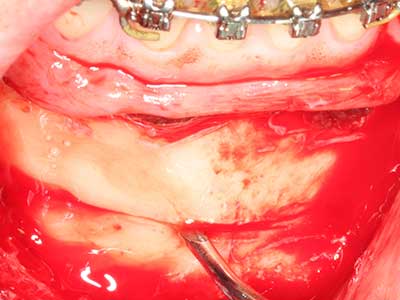

Пиезохирургията има допълнителни предимства при събиране на костни блокове. В допълнение към високата прецизност при остеотомията, описана по-горе, употребата на фините режещи накрайници значително намаляват загубата на материал. Голяма загуба на материал по време на събиране може да се очаква с дебелите накрайници, особено при употреба на борери Линдеман (Lakshmiganthan, Gokulanathan et al. 2012). Базалното разделяне, което е необходимо, особено за присадка на блок при ретромолар, е улеснено от специално създадени правоъгълни триони. В резултат на това, пиезохирургията е разглеждана като прецизна, улеснена и безопасна процедура за събиране на костни блокове в ретромоларното пространство (Happe 2007) (Фиг. 1-12).

Костната тъкан е не само минерализирана структура, тя съдържа и съществено количество колагенови влакна. Това означава, че тя има не само добра компресивна сила, но и известна степен на гъвкавост, която може да се възприеме като предимство при извършване на костна аугментация. В класическата процедура по разширяване чрез костно разделяне, атрофиралият алвеоларен гребен е разделен надлъжно и внимателно разширен след достигане на подходящата остеотомна дълбочина (Фиг. 13-16), в идеалния случай без допълнително отстраняване на периостеума (Brugnami, Caiazzo et al. 2014, Stricker, Fleiner et al. 2014). Системите с винт и пластини с увеличаване на разстоянието при разширяване са доказали ефективността си при разделяне на двете костни ламели, оставайки под прага на фрактурите. В общи линии, оставащата ширина на костта от поне 3–4 mm е задължителна (Chiapasco, Zaniboni et al. 2006), за да се гарантира добра гъвкавост и достатъчно костно покритие за бъдещото поставяне на импланти. Ако е необходимо, вертикалната остеотомия на едната или двете страни може да подобри гъвкавостта. Комбинацията с допълнителни техники за аугментация, особено в букалната страна, е описана като алтернатива на класическата техника.

Процедурата по разделяне е атравматична и няма голяма загуба на пространство, използвайки пиезотриони, и няма значителна разлика между импланти в разделени челюсти и импланти в алвеоларния гребен без костен дефицит (Chiapasco, Zaniboni et al. 2006, Danza, Guidi et al. 2009). Въпреки това, важно е да има достатъчно и продължително охлаждане, особено при ограничено и дълбоко разделяне, за да се избегне термичен стрес в апикално-остеотомните зони.